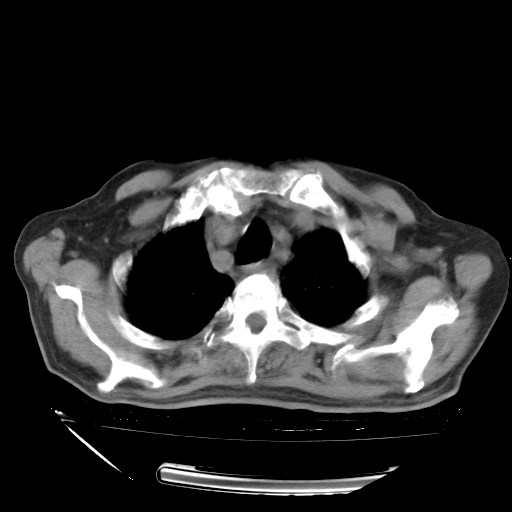

甲强龙80mg/日+抗结核治疗(异烟肼+利福霉素+乙胺丁醇)10天。复查肺部CT。

治疗10天肺部CT